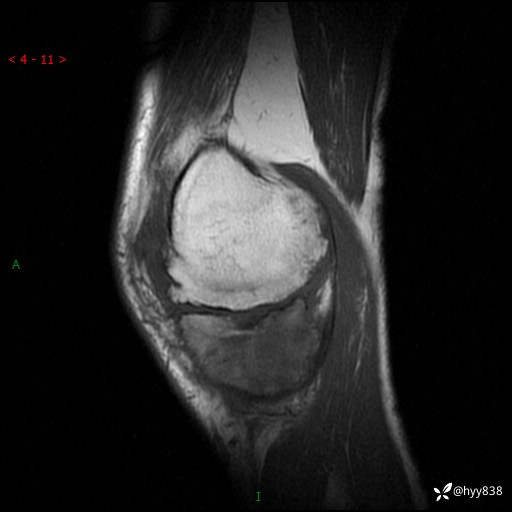

MRI(sag :T1WI+T2WIfs)